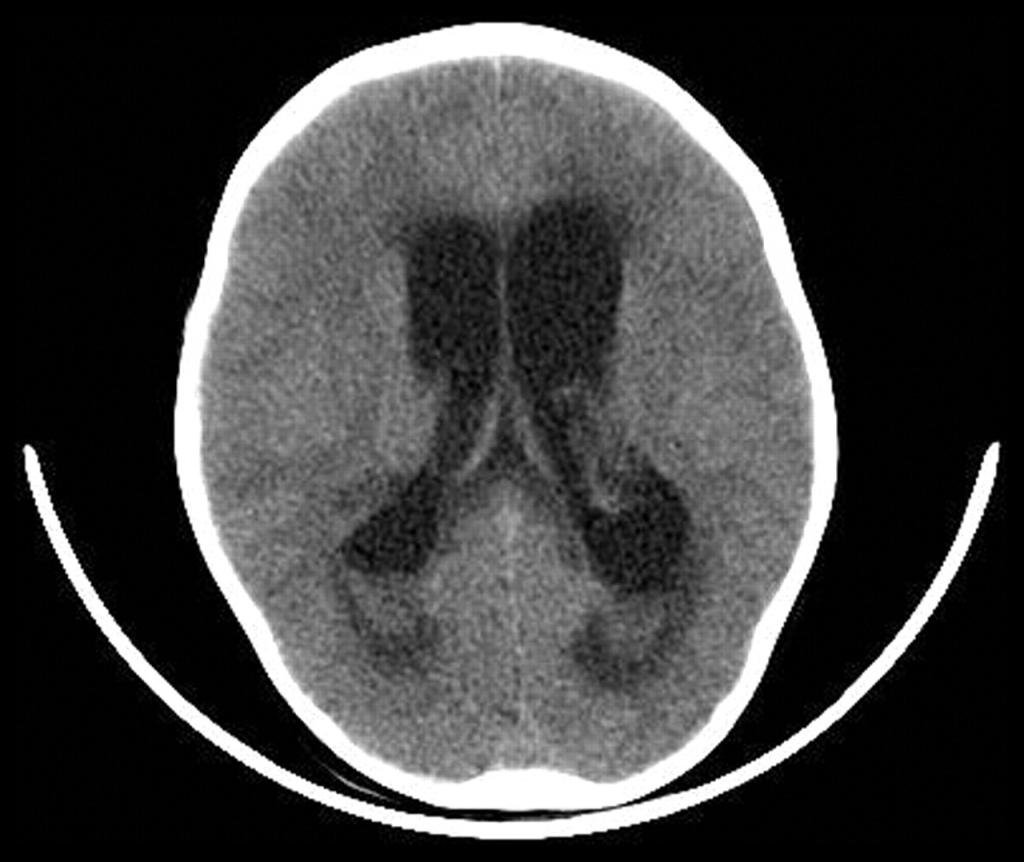

- компьютерная томография (КТ) и магнитно-резонансная томография (МРТ) головного мозга;

- компьютерная томография;

- МРТ и КТ.